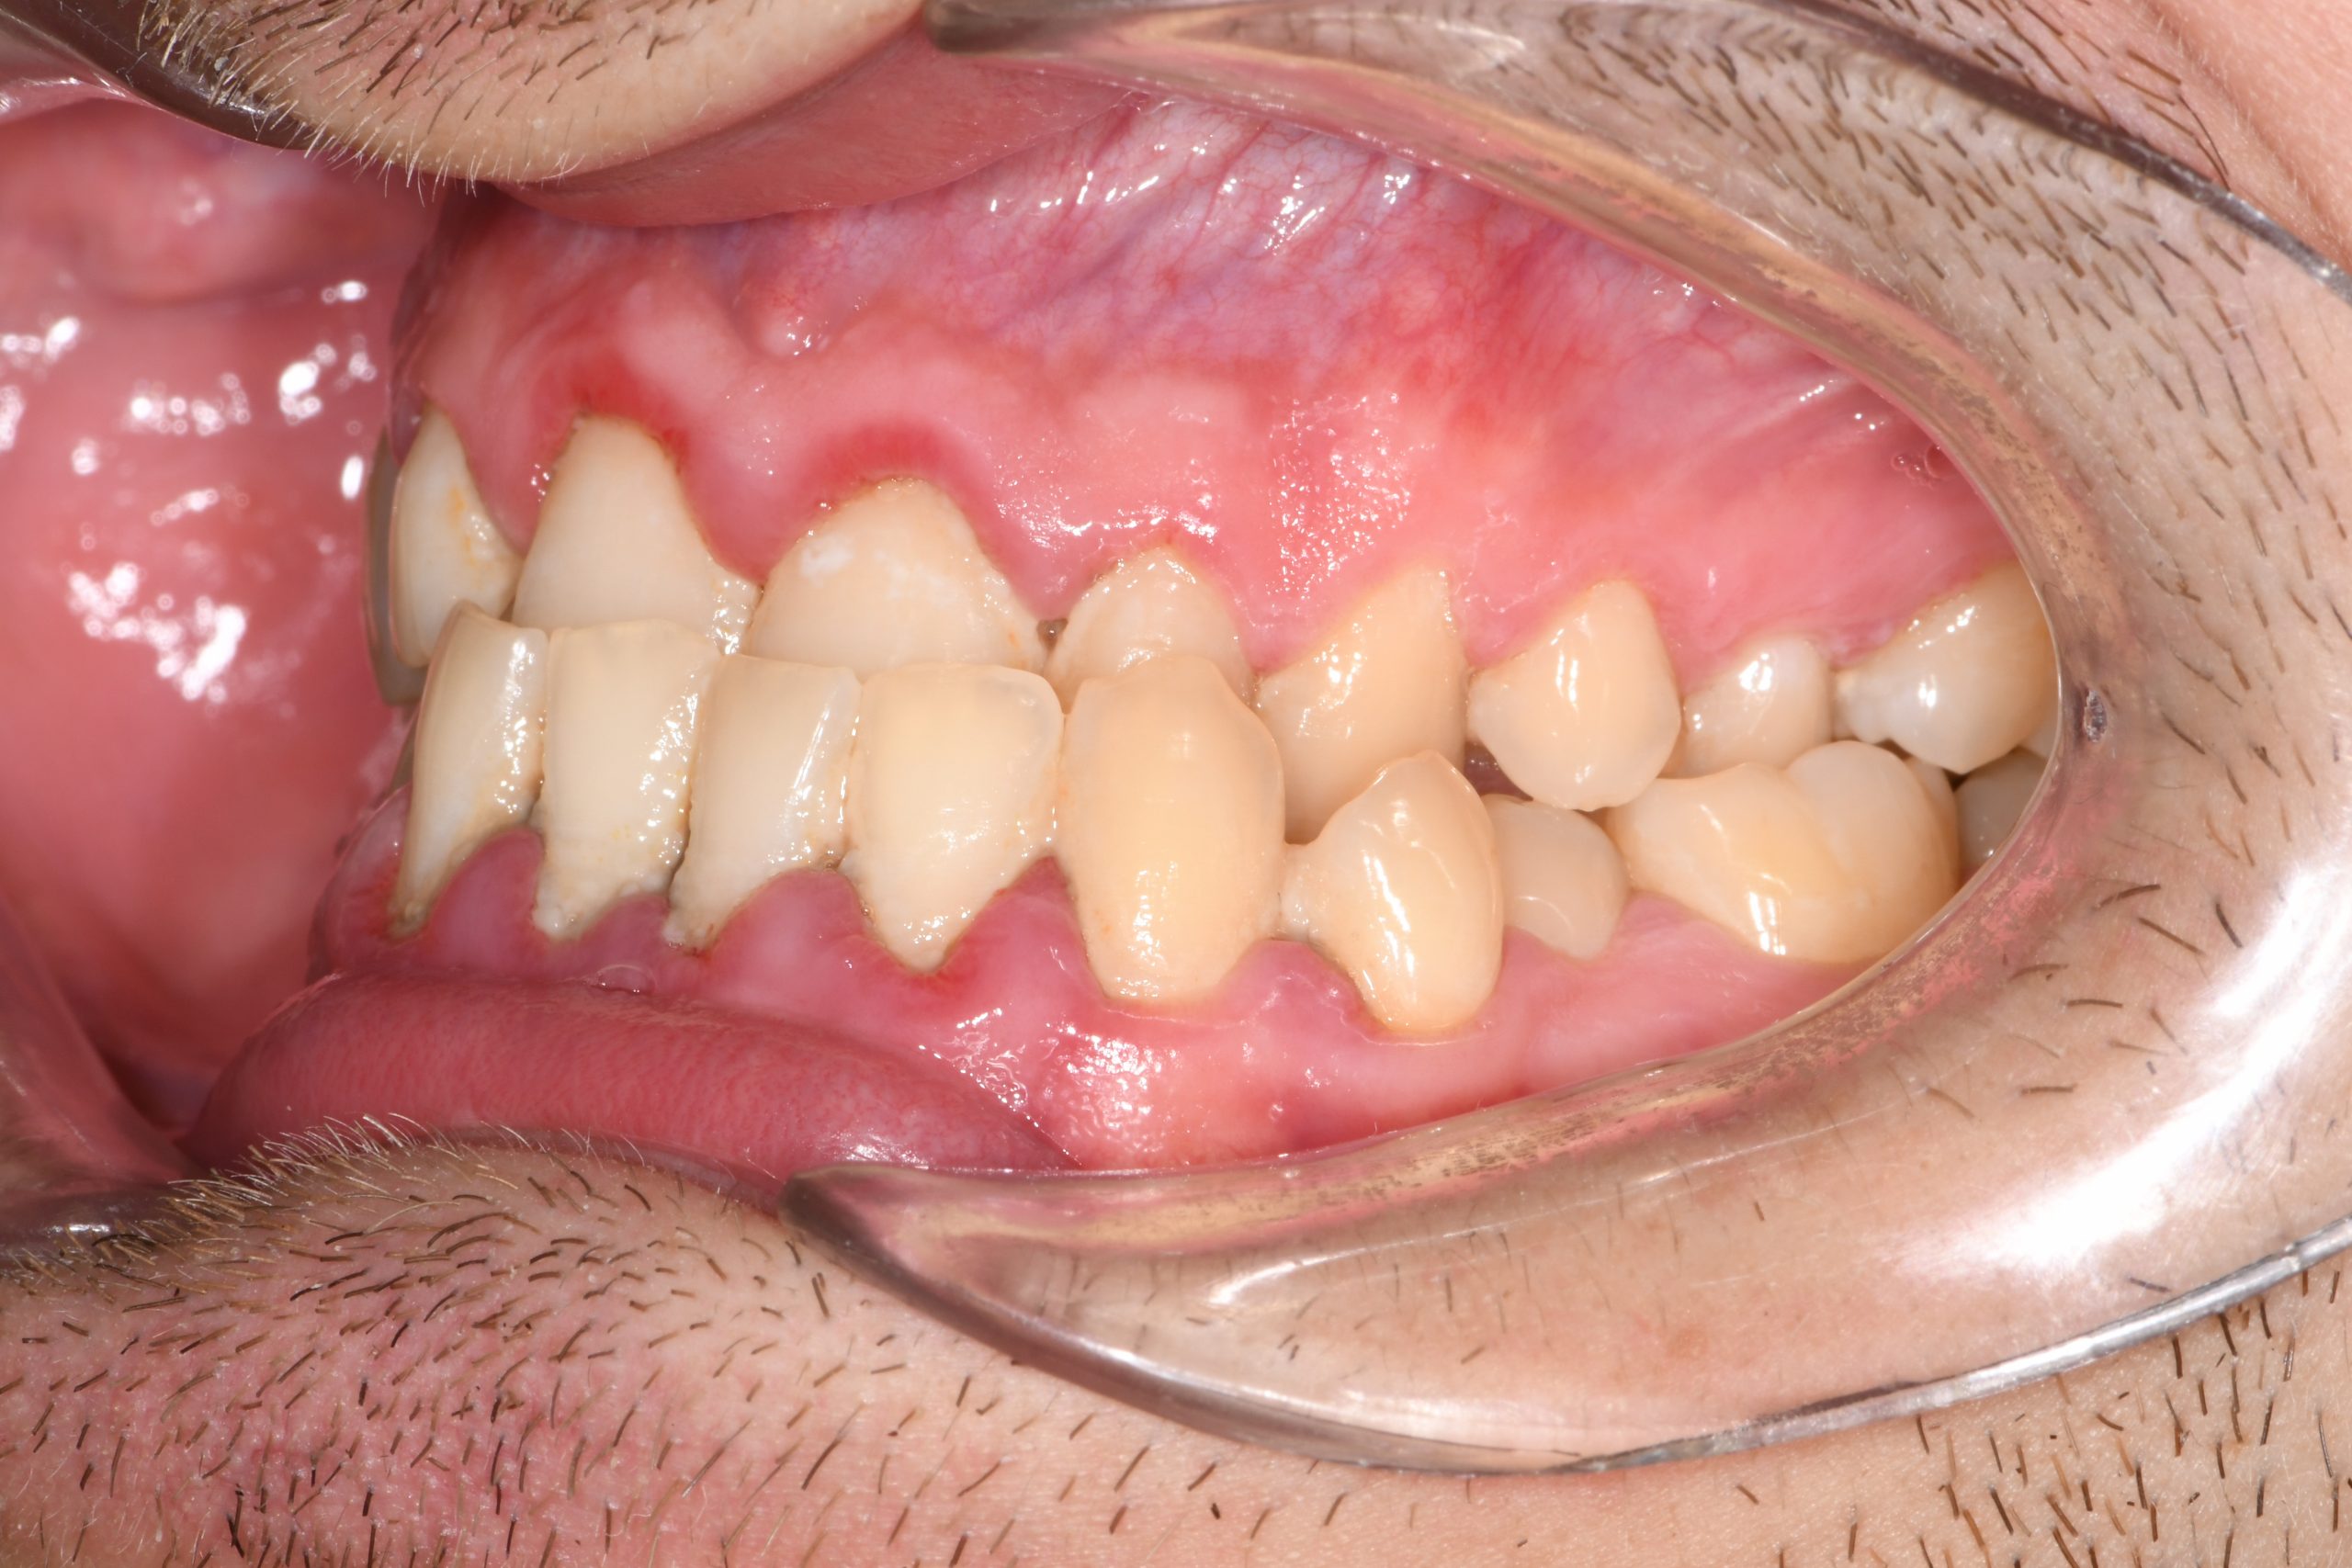

Az elmúlt évekből rengeteg szakmai referenciát tudnánk bemutatni, amelyek különböző fogszabályozási problémákat oldottak meg. Válogatva a több száz esetből, ezen az oldalon olyan képeket, információkat igyekeztünk bemutatni, amelyeknek a segítségével a jövőbeni pácienseinknek azt tudjuk üzenni: A Te fogsorod is lehet gyönyörű!

(Képeket a Pácienseink külön írásos beleegyezésével mutatjuk be!)